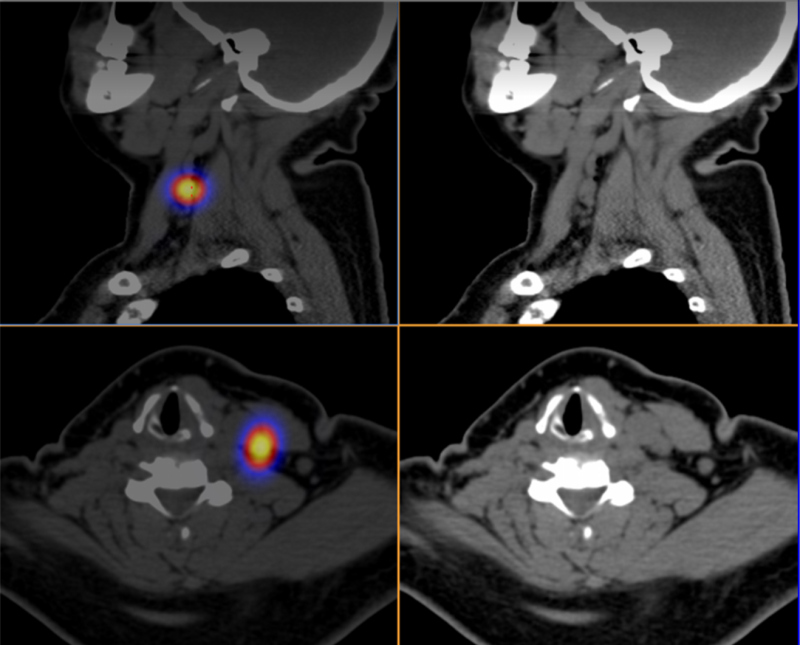

Las figs 2-5 ilustran casos de la serie analizada.